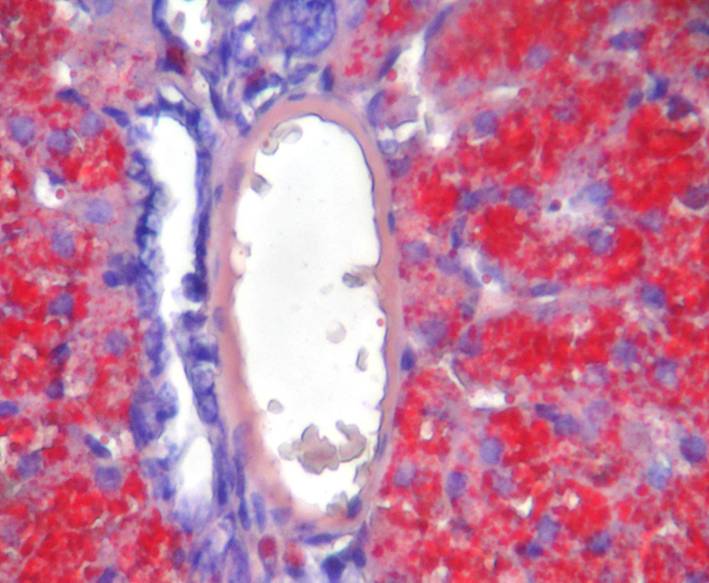

【染色結(jié)果】脂肪被染成鮮紅色,細(xì)胞核染成深藍(lán)色,其他組織被染成淡藍(lán)色。